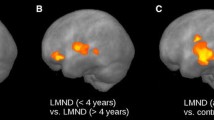

The comparison at the group level by WBSS of FA maps for flail arm syndrome patients vs controls demonstrated several clusters of regional alterations at p < 0.05 (corrected for multiple comparisons). Maps of FA reductions are depicted in Fig. 1 for the group comparisons. When comparing flail arm syndrome patients and controls, regional FA reduction was observe in the upper CST (corresponding to neuropathological stage 1 of ALS); the identical FA reduction pattern was observed in the comparison of ALS patients vs controls. The comparison of flail arm syndrome patients and ALS patients revealed only small quantitative differences bihemispherically along the central and upper CST. A summary of all significant clusters at the group level is provided in Table 2.

Whole brain-based spatial statistics (WBSS) of FA maps of flail arm syndrome patients and ALS patients vs controls. WBSS of FA maps [p < 0.05, false-discovery-rate (FDR) corrected] demonstrated clusters of regional FA reductions for flail arm syndrome patients vs controls as well as for ALS patients vs controls predominantly along the corticospinal tract (CST)